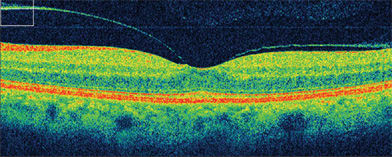

The most onerous postoperative aspect for the patient remains the need for face-down positioning. In the 1990s, face-down positioning was recommended for at least 2 weeks, but a trend toward a shorter interval seems still to yield similar outcomes.6,7 Surgical success rates include anatomic success rates well into the mid-90% range and visual improvement in about 80%. Optical coherence tomography (OCT) has advanced the diagnostic accuracy (Figure 2) of this condition,8 as there are many conditions mimicking the clinical appearance of macular holes.9

Figure 2. Spectral-domain OCT of macular hole in patient shown in Figure 1. Visual acuity is 20/200 in the right eye.